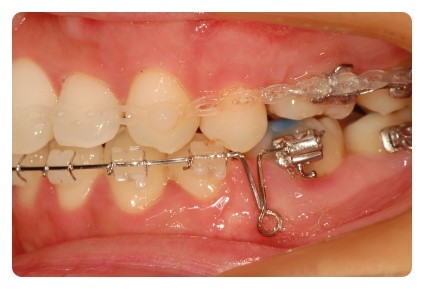

옆모습은 가지런하게 잘 진행중

그런데 브라켓이랑 송곳니가 자꾸 부딪쳐서 치아가 조금 깨진것같기도 하구

송곳니가 원래 저렇게 뾰족했던가 ??